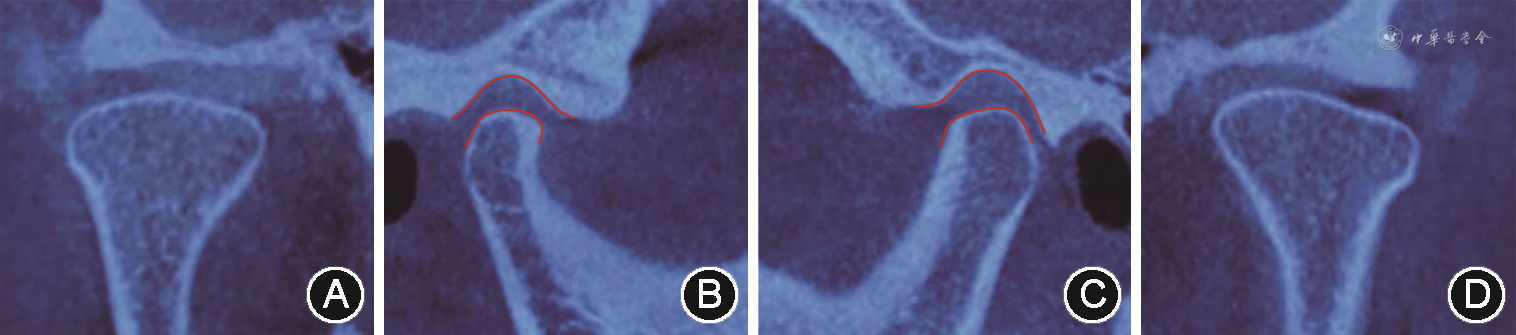

垫后关节CT A:右侧髁突冠状位;B:右侧髁突矢状位,红色线条间空隙示右侧颞下颌关节前间隙较治疗前缩小;C:左侧髁突矢状位,红色线条间空隙示左侧颞下颌关节前间隙较治疗前增大;D:左侧髁突冠状位

垫后关节CT A:右侧髁突冠状位;B:右侧髁突矢状位,红色线条间空隙示右侧颞下颌关节前间隙较治疗前缩小;C:左侧髁突矢状位,红色线条间空隙示左侧颞下颌关节前间隙较治疗前增大;D:左侧髁突冠状位(4)诊断性临时修复:借助电子面弓记录患者关节及下颌运动轨迹,获取个性化动态数据(左侧方8.1 mm,右侧方9.9 mm;前伸4.6 mm;侧方髁道右侧14.1 mm,左侧14.2 mm;侧方髁道斜度右侧44°,左侧29°),通过多次开闭口运动,寻找患者的正中关系并记录颌位关系。最后根据这些参数调整虚拟